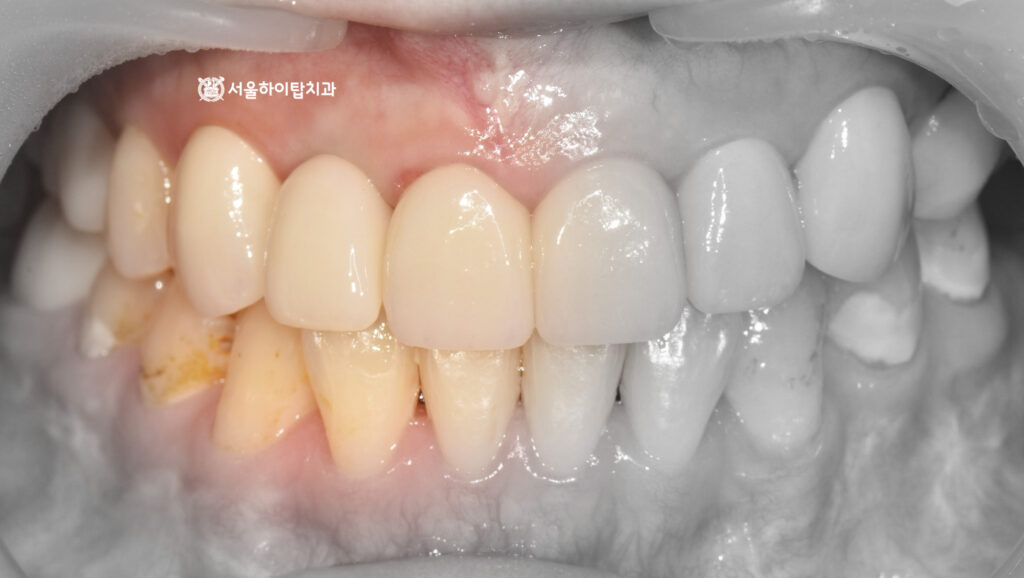

최종 보철 – 지르코니아 크라운 장착

앞서 진행한 쉐이드 체크를 통해 주변 자연치와 조화롭게 어울리는 색상을 선택되었으며,

이 데이터를 바탕으로 최종 지르코니아 크라운을 제작하여 장착한 모습입니다.

파노라마 엑스레이에서도, 픽스처가 골 속에 단단히 심겨져

안정적인 모습을 확인할 수 있으며,

주변 치아와도 조화로운 배열을 이루고 있음을 확인할 수 있습니다.